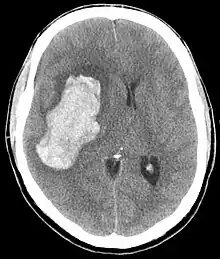

Saignement intra-parenchymateux avec œdème

En général, les valeurs de pression artérielle systolique sont très élevées sans qu'il y ait de valeur seuil (200 à 300 mmHg), par contre en termes de diastolique, on retrouve des valeurs supérieures à 120 mmHg voire 130 mmHg. L'évolution ou les variations tensionnelles peuvent également être importantes.